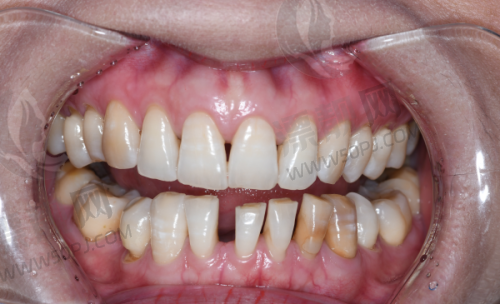

二、设备精良不打折,“拿得出手”的技术不是空谈

现在口腔诊疗讲究一个字:精!而瑞兴口腔医院引进了多种进口高端诊疗设备,比如数字化3D种植导航、口腔CT、显微镜种牙、德国西诺德牙椅等。别小看这些“电动玩具”,确实改变了过去只靠眼就是干的时代,精度高、创伤小、修复快,还能事前3D建模、精密植入,真正做到”种牙不靠瞎蒙,全靠导航定位”。要知道,在上海要配齐这些设备的私立医院,可没几家。